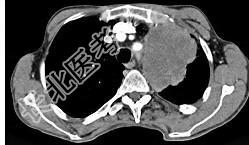

- 单项选择题56岁,男, 意识错乱情绪不稳定一周,请结合胸片和CT, 选出最可能的诊断 ( )

A、肺癌

B、错构瘤

C、胸内甲状腺肿

D、韦格肉芽肿

E、胸腺瘤